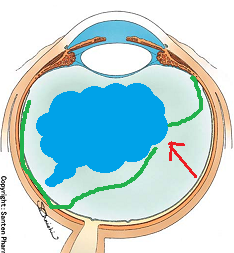

黒目(角膜)から入ってきた光は、目の奥の方のフィルム(網膜)に当たります。網膜は一つの束(視神経)になって、最終的には脳ミソにつながり、「物が見える」という事になります。

図の赤矢印の部分は視神経乳頭と言って、網膜が集まって束になる部分なのですが、実はこの部位のみ光を感じ取ることはできないのです。

写真だと水色の部分が視神経乳頭(マ盲点)になります。ちなみに、物を見る中心部の網膜は黄斑と呼ばれ、オレンジの矢印に当たります。